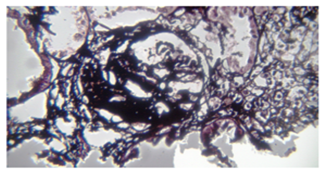

Since the patient was too ill to be transferred to CT-scan department all diagnostic procedures were performed portable on the bedside. We had the chance of having definite serial ultrasonographic checks of abdominal and pelvic cavities indicating that we could be sure of not having any kind of abnormal internal bleeding. This fact helped our obstetrician not to perform second revision of the site of operation. Laboratory findings including: ANA, FANA, Anti dsDNA, APA, C3, C4, CH50, HBS Ag, Anti HCV Ab, Anti HIV, lupus anticoagulant, anticardiolipin and serum albumin were not abnormal. ADAMTS 13 Ag 5.22 high ADAMTS 13 auto Ab 14.4 borderline verifying in blood sample. Complications due to invasive procedures at the time of patient’s presentation to hospital, she was suffering from mild to moderate respiratory distress investigation by chest x-ray and chest sonography indicated moderate bilateral pleural effusion. In addition after replacement of shaldon catheter on the day of admission, we had right sided hemopnuemothorax leading to insertion of chest tube, on day9, chest tube discharge was less than 100cc/24h and on day 12 we removed it. Biopsy sample taken from kidney 3months after hospitalization. The glomerulus shows segmental sclerosis with synechiae to overlying, Bowman’s capsule (methenamine silver, x400) (Figure 1, Figure 2 & Figure 3).

Figure 1 The glomerulus shows segmental sclerosis with synechiae to overlying, Bowman’s capsule.

Figure 2 The glomerulus shows segmental sclerosis with synechiae to overlying, Bowman’s capsule.

Figure 3 The glomerulus shows segmental sclerosis with synechiae to overlying, Bowman’s capsule.